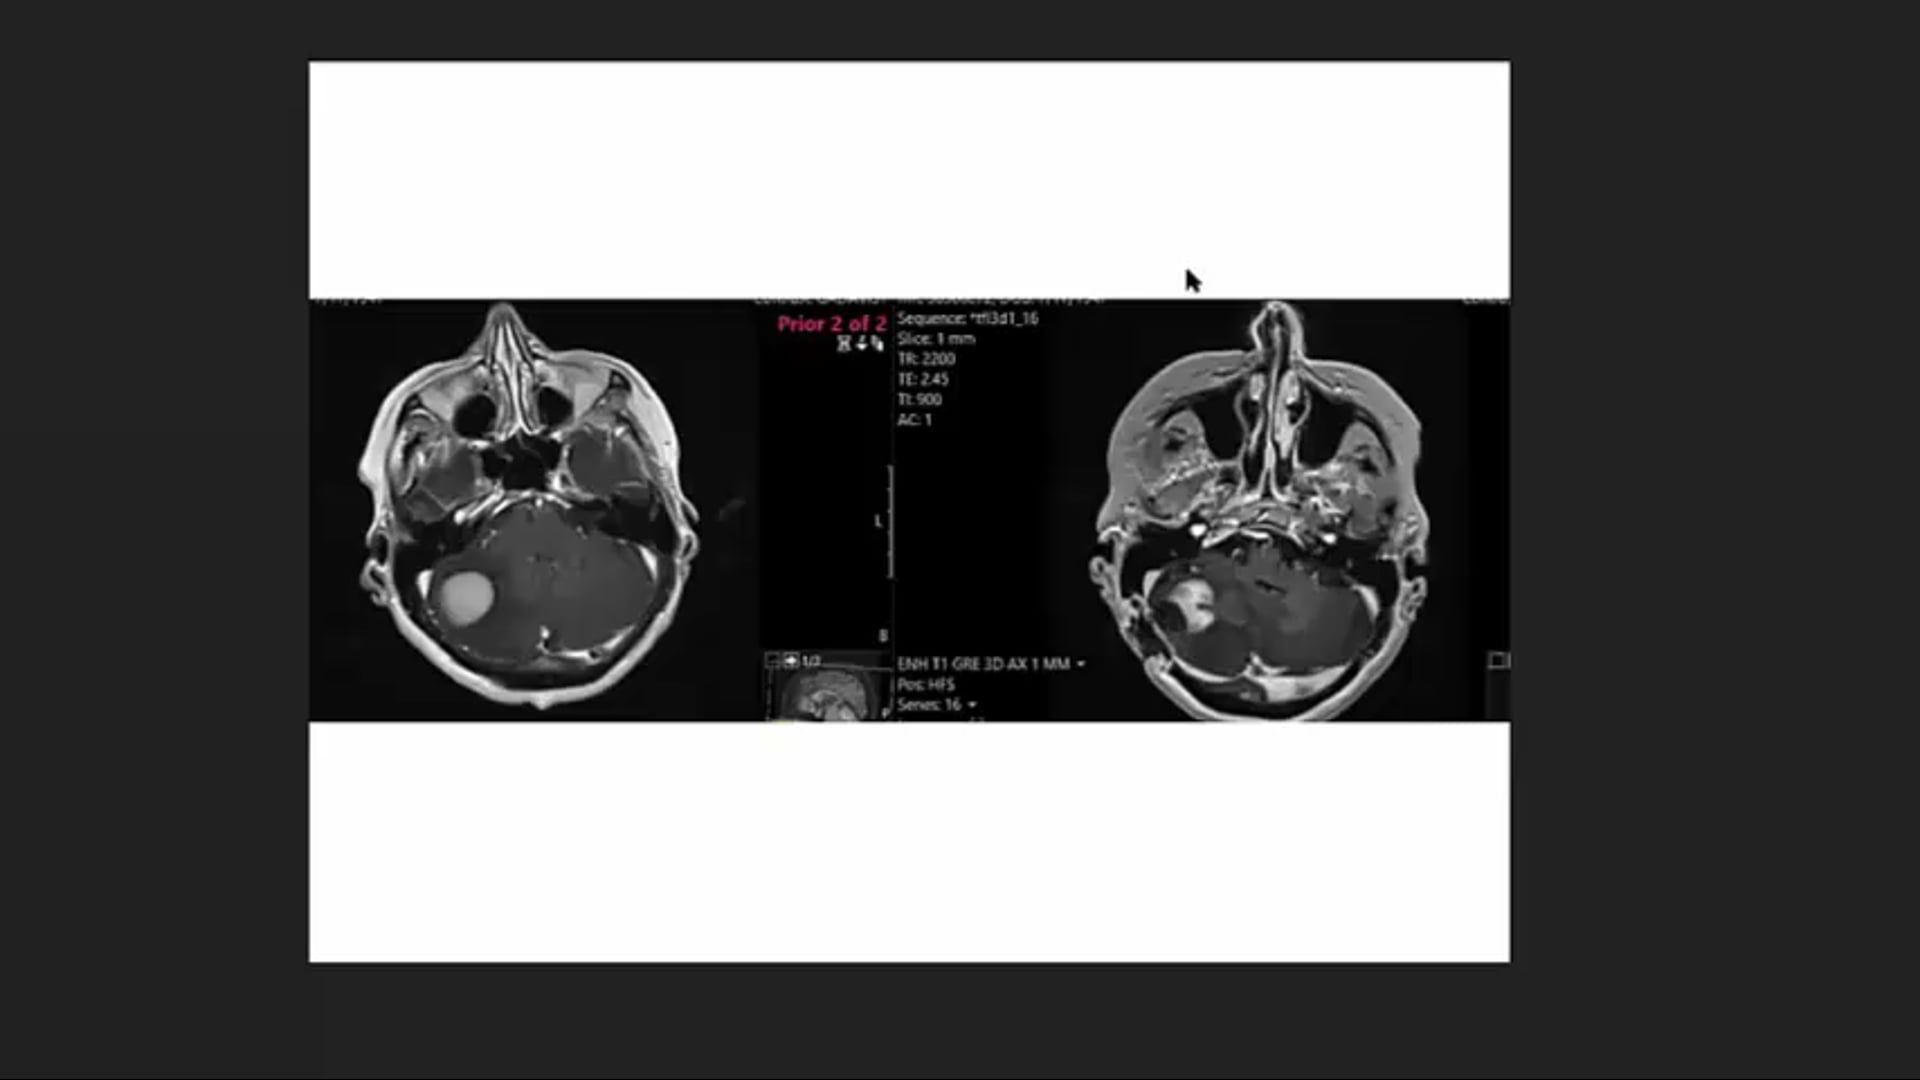

04/21/21 - Dr. Andrea Ng - Radiation Oncology - Lymphoma

05/12/21 - Dr. Andrea Ng - Radiation Oncology - Lymphoma

Lymphoma radiation, dose, local palliation, CTV